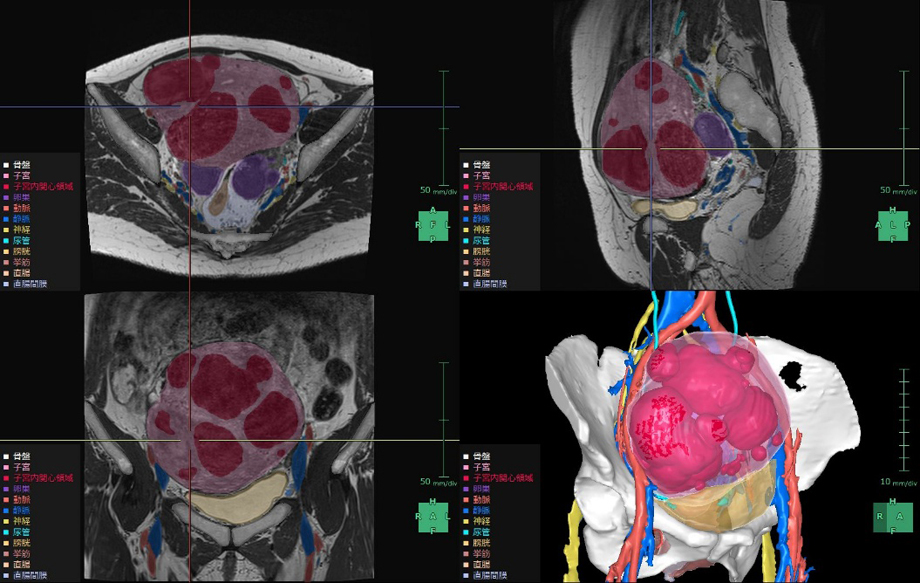

今回提供を開始する「SYNAPSE VINCENT Ver7.3」では、これまでに提供している「直腸解析」に加え、子宮や卵巣領域の術前シミュレーションを想定した「婦人科臓器解析」、膀胱や前立腺の術前シミュレーションを想定した「膀胱周辺臓器解析」を新たにラインアップする。

いずれの解析機能も、CT画像やMR画像からの臓器セグメンテーションおよび3D画像解析において同社のAI技術*2を活用している。今回、骨盤内臓器に対する術前シミュレーションを幅広くサポートできるようになり、骨盤外科領域に本格参入する。

子宮筋腫は、成人女性の罹患率が20~30%と高頻度に見られる疾患*4で、機能温存が重要とされている。MRIや超音波画像診断装置の2D画像では筋腫や周囲組織の3次元的な把握が難しく、骨盤内の複雑な解剖構造の理解も困難である。また、筋腫の大きさや数、妊孕性温存の希望などにより様々な手技が適用されるが、筋腫の計測や手技の選択は各医師の経験則や感覚に基づいて行われているという課題がある。「婦人科臓器解析」ではMRIのT2画像からAI技術*2を活用した抽出エンジンを用いて子宮周囲の臓器をセグメンテーションし、ユーザーが子宮筋腫と判断した箇所の体積・数・深さの定量化を行うことができる。また、3Dで周辺組織との位置関係を把握することで筋腫手術の低侵襲化や取り残し防止等への寄与が期待される。